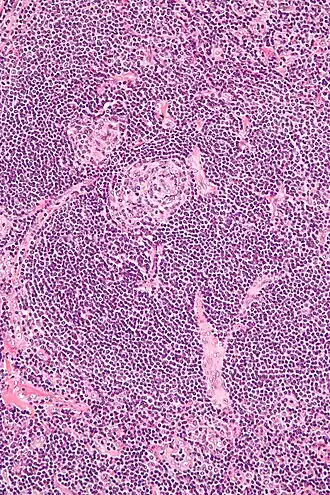

L'histologie (biopsie ostéomédullaire) montre des lésions qui peuvent orienter le diagnostic, associant une hyperplasie lymphatique et vasculaire, une plasmocytose, des atypies sur les mégacaryocytes, une fibrose. Toutefois, ces constatations ne sont pas spécifiques[12] et les données histologiques ne permettent pas d'orienter le traitement médicamenteux[13].